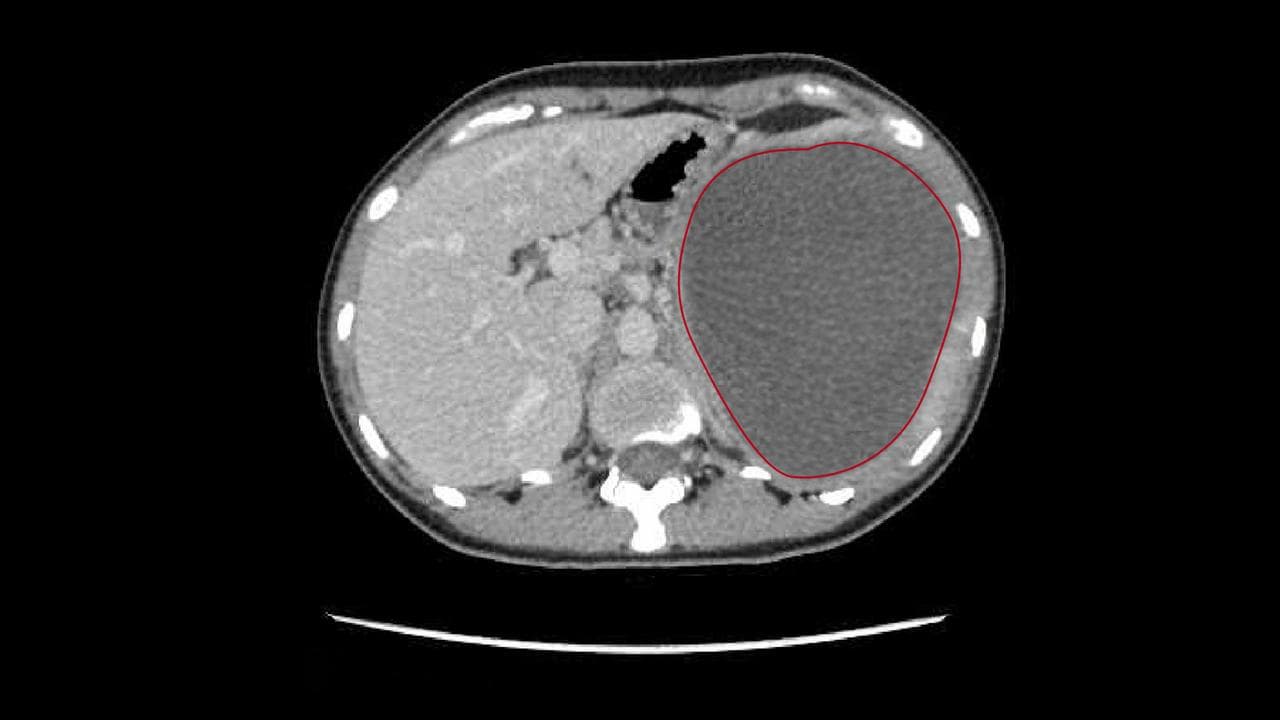

The 29-year-old had no idea it was a potentially fatal watermelon-sized parasitic cyst growing on her liver.

The main concern was the watermelon-sized cyst on her liver.

Two secondary cysts - the size of a rockmelon and a tennis ball respectively - were also removed.